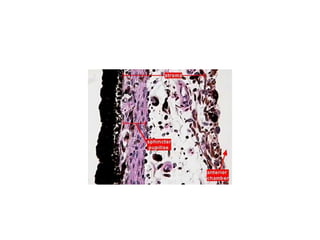

• The choroid (40X) has four histological layers.

• Suprachoroid. This is an avascular layer of loose

C.T., melanocytes and nerves.

• Vascular layer. (100X) This layer is characterized

by prominent veins and small arteries (20X).

• Choriocapillaris (Choriocapillary layer). (100X)

The capillaries in this layer directly nourish the

outer half of the retina.

• Basal layer, or Brüch's membrane. (100X) This

structure is the basement membrane of the

retinal pigment epithelium.

Choroid

Vascular layer

Retina

Choriocapillaris